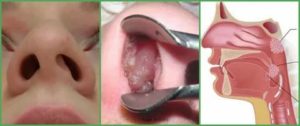

При храпении у ребенка по ночам диагностируются врожденные аномалии строения носоглотки: дефекты и деформации неба, искривленная перегородка носа. У 90 % детей храп обусловлен гипертрофией лимфоидной ткани в носу и аденоидами, поэтому зачастую специалисты настаивают на аденотомии — удалении носоглоточных миндалин.

- Искривленная носовая перегородка, врожденная узость носовых проходов;

- Анатомические особенности строения черепа — маленький, скошенный назад подбородок, увеличенный язычок небной занавески (из-за появления воспаления после иссечения);

Рассматриваемое состояние носит хронический характер. При таком диагнозе существует высокий риск развития обструкции дыхательных путей. Процесс сопровождается гипертрофией лимфоидной ткани.

Воспаление распространяется на ротовую и носовую полость, стенки глотки. Причины, на фоне которых состояние ребенка усугубляется:

- аномалия лица, челюсти;

- гипертрофия языка, миндалин.

Аденоиды – результат разрастания тканей глоточной миндалины. Такое явление чаще всего встречается у детей в возрасте от 3 до 12 лет, но иногда возникает и у младенцев.

Глоточная миндалина – скопление лимфоидной ткани, которая в норме является частью иммунной системы. Эта структура противостоит патогенным микроорганизмам, которые стремятся проникнуть в организм.

Симптомами разрастания тканей миндалины являются храп и приступы ночного удушья, сухой кашель в утреннее время, продолжительный насморк, затрудненное носовое дыхание, гнусавость голоса.